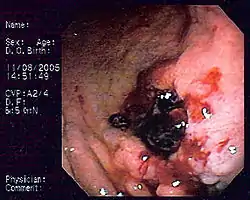

![]() Billede af kræft i lymfeknude | |